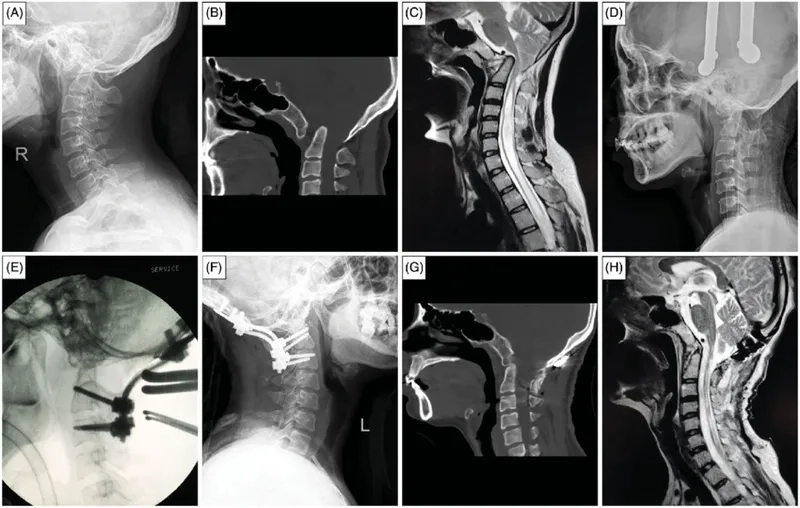

• The primary treatment is often syringomyelia surgery to correct the underlying cause, such as a Chiari malformation, and restore normal fluid flow.

• Regular monitoring with MRI scans is essential to track the size and progression of the syrinx and determine the best timing for surgical intervention.

A before-and-after MRI following syringomyelia treatment